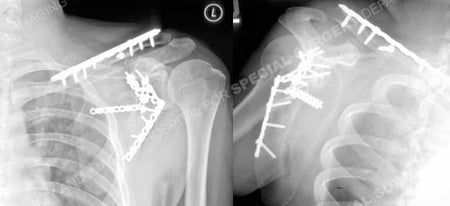

He was then transferred to the care of David L. Helfet, MD at the Orthopedic Trauma Service of Hospital for Special Surgery for definitive management of his scapula fracture. ORIF was performed for his scapula fracture with placement of multiple mini-fragment plates and screws including interfragmentary lag screws. He continued to return for regular follow-up and his fractures healed uneventfully and at 1 year following fracture surgery his results are excellent including healed scapula and clavicle fractures, full resolution of pain and range of motion, and a return to all his pre-injury activities.

Radiographs at 1 year revealing healed scapula and clavicle fractures in excellent alignment.